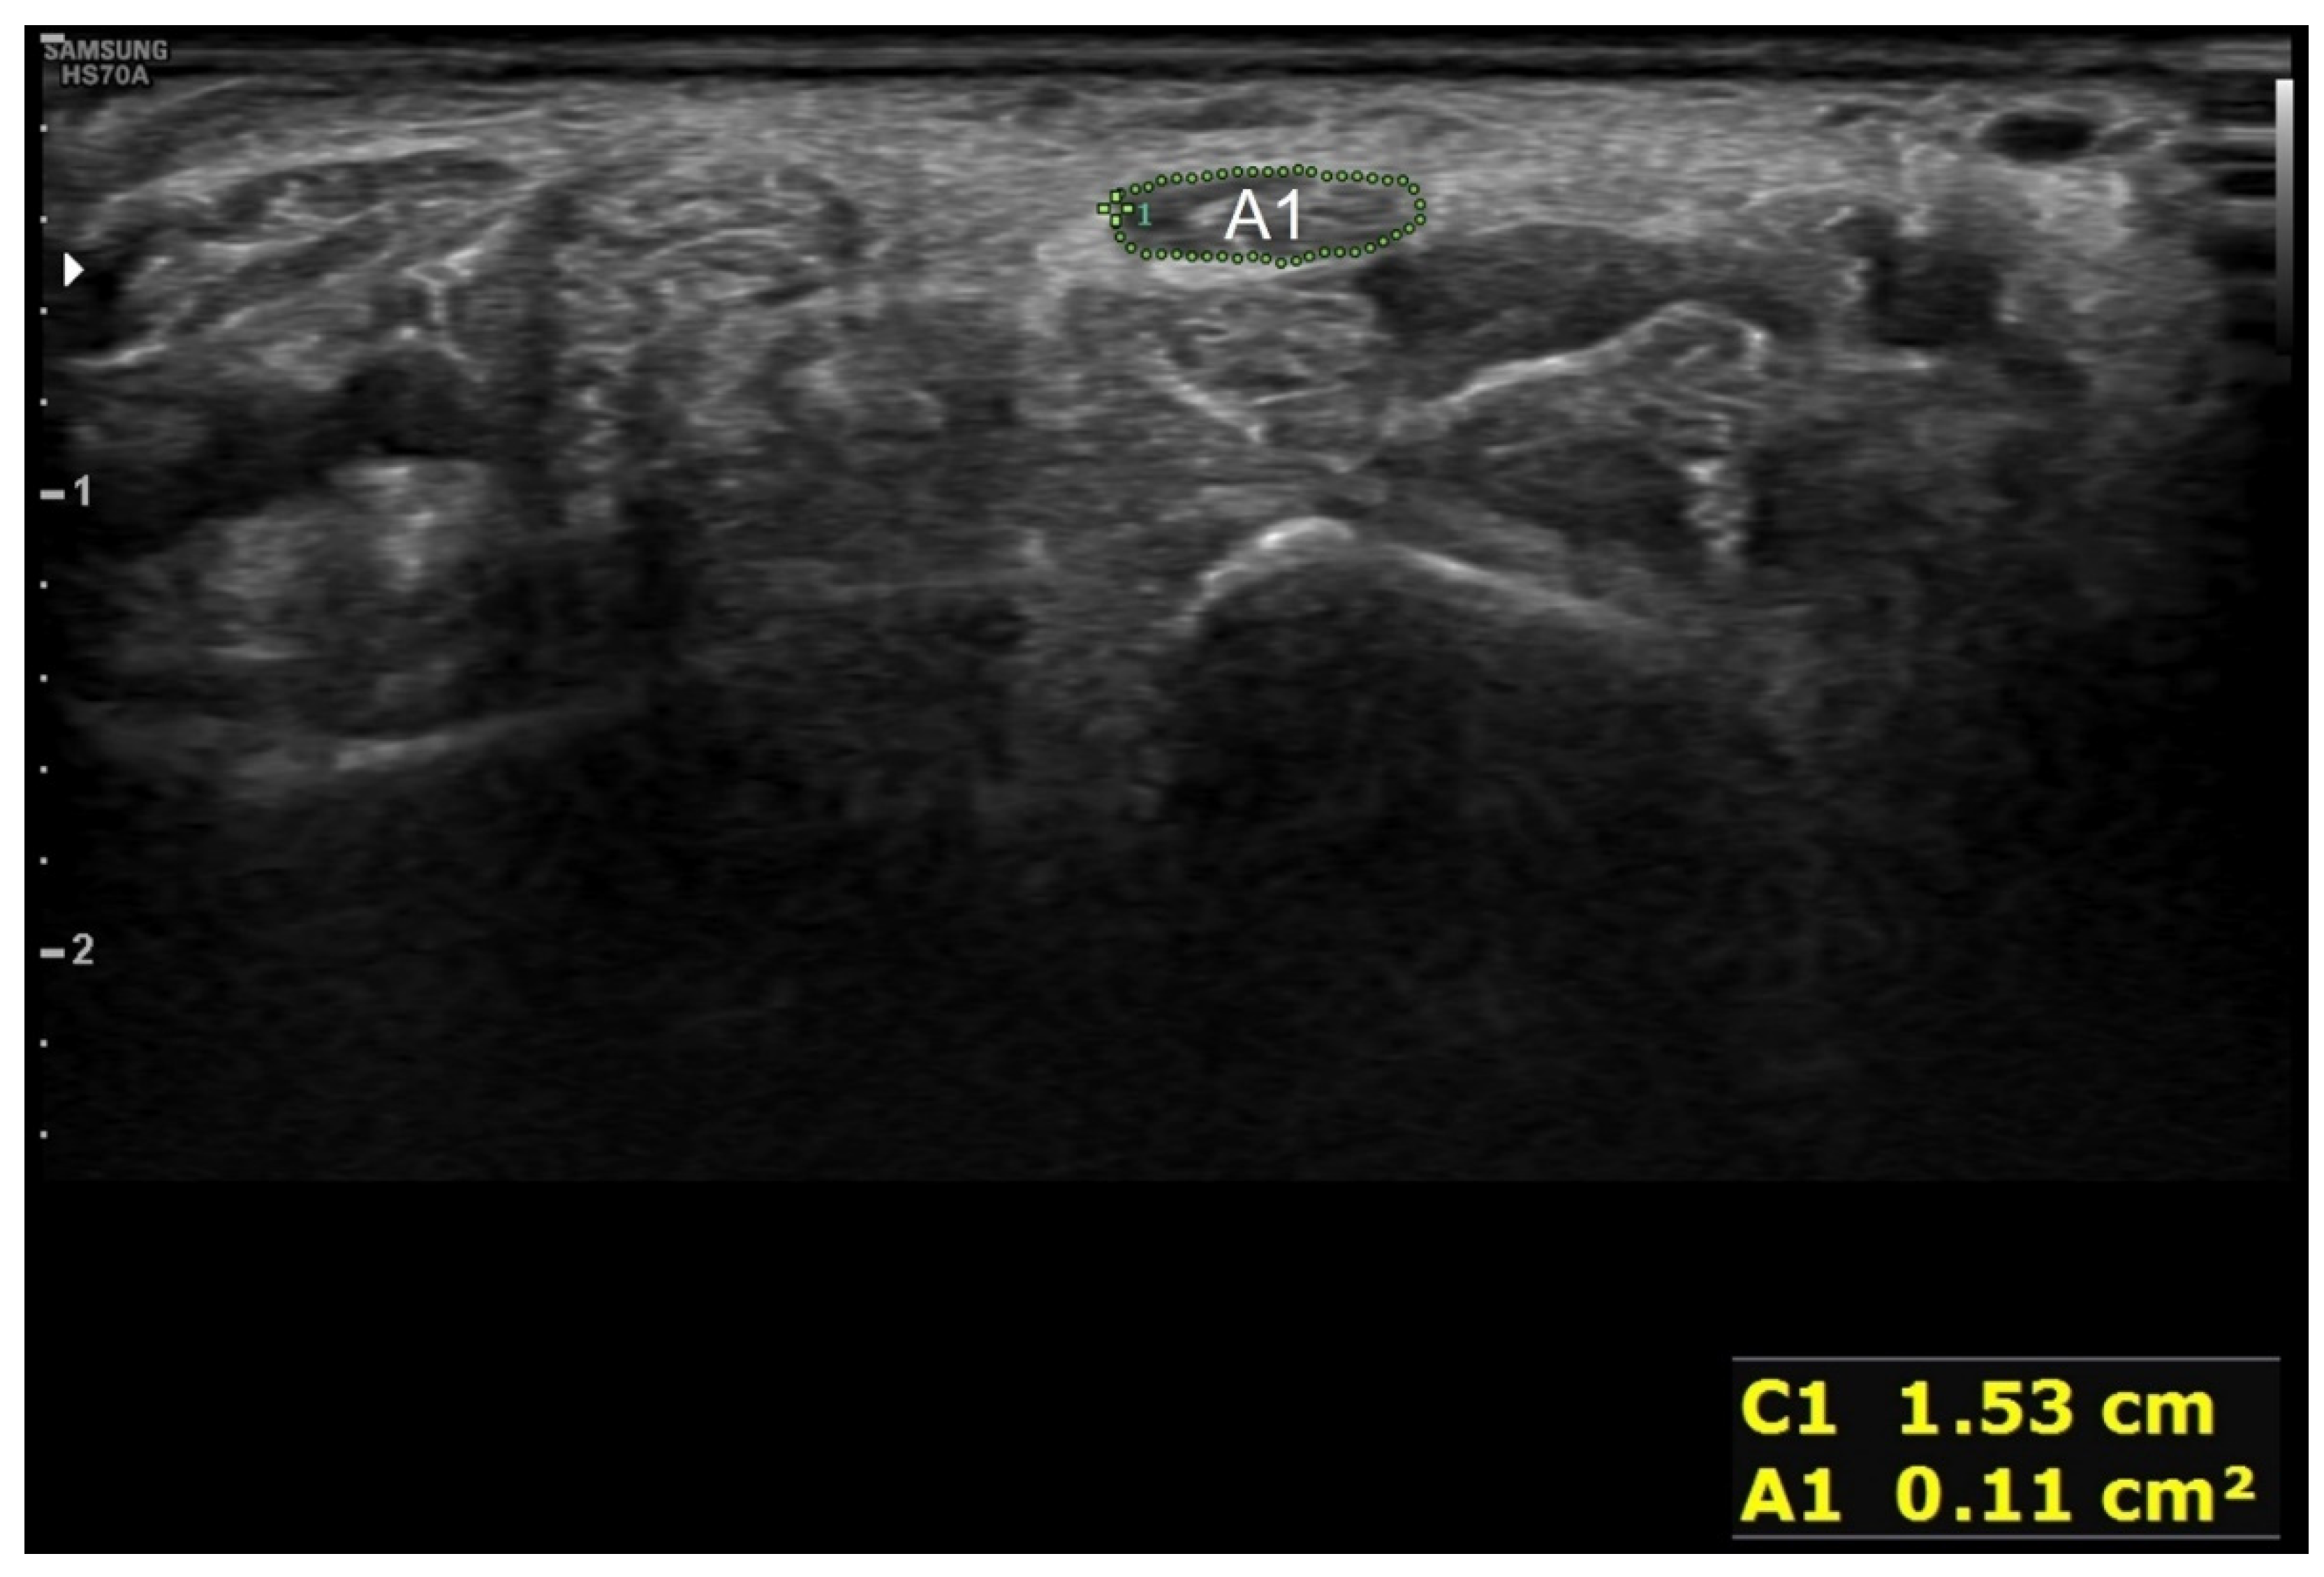

| 12. Correct measurement of the cross-sectional area of the median nerve and explaining the examination results | 3 | 1.65 ± 1.19 | |

| 12–1. Correct measurement of the cross-sectional area of the median nerve proximal to the flexor retinaculum | 2 | 1.07 ± 0.83 | |

| 12–2. Explaining the examination results | 1 | 0.58 ± 0.50 | |